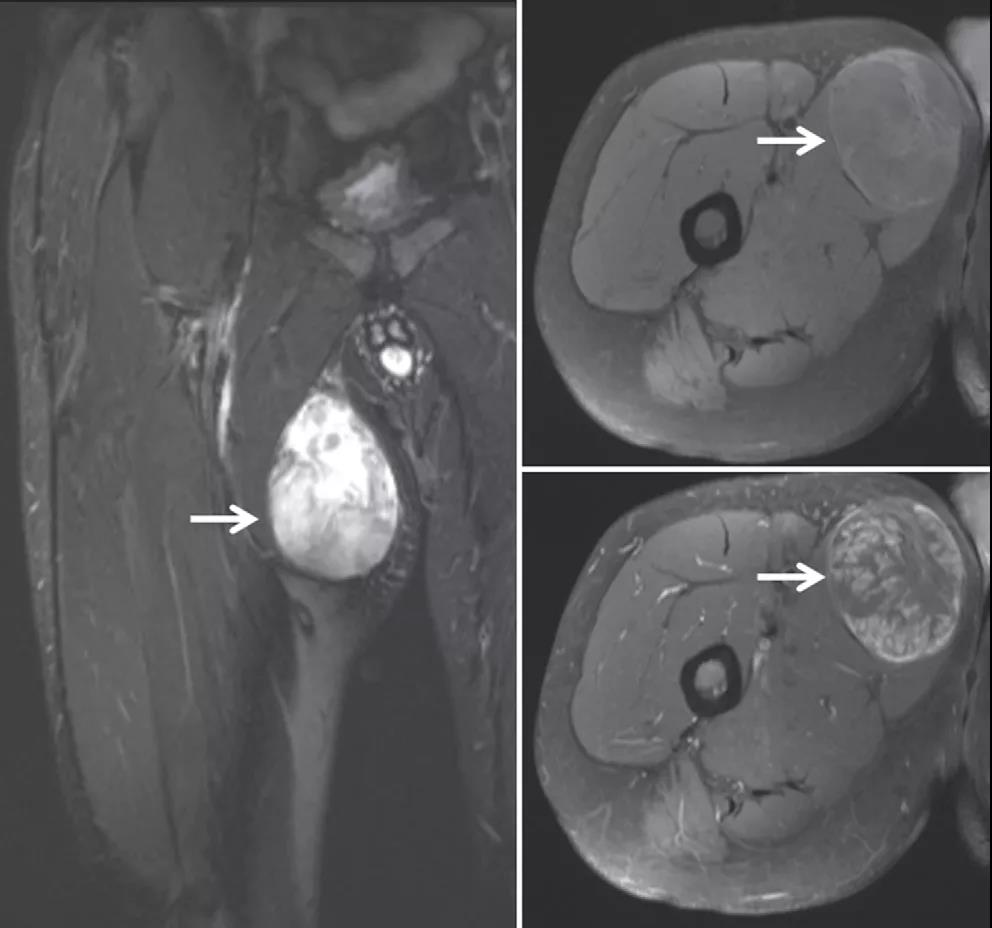

多形型脂肪肉瘤:较罕见,多在四肢出现,躯干或腹膜后出现较少。

生长在腿部的脂肪肉瘤会导致皮肤下出现肿块,疼痛肿胀,肢体无力。

目前的诊断方法一般是通过影像学检查如X射线、CT扫描和MRI(磁共振成像)确定肉瘤的大小和发展程度,其次是通过活检、荧光原位杂交和分子遗传学方法等确定癌细胞类型,并制定相应的诊疗方案。